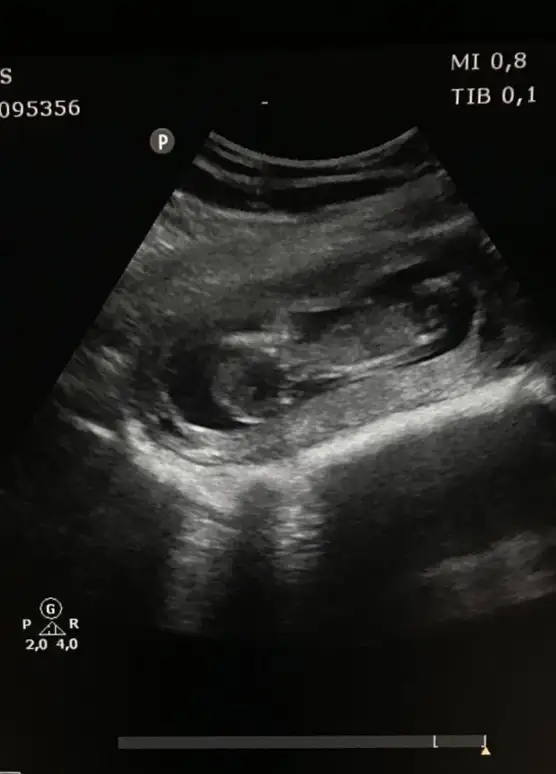

Ben burayı nasıl kaçırmışım.En son ultrason resmimiz 11+3 'ten.Tahmin alabilir miyim arkadaslar![]()

Çoook teşekkür ederim canım evet sen söylemistin❤Evet erkek tahmin etmişim saglıkla gelsin ogluş![]()